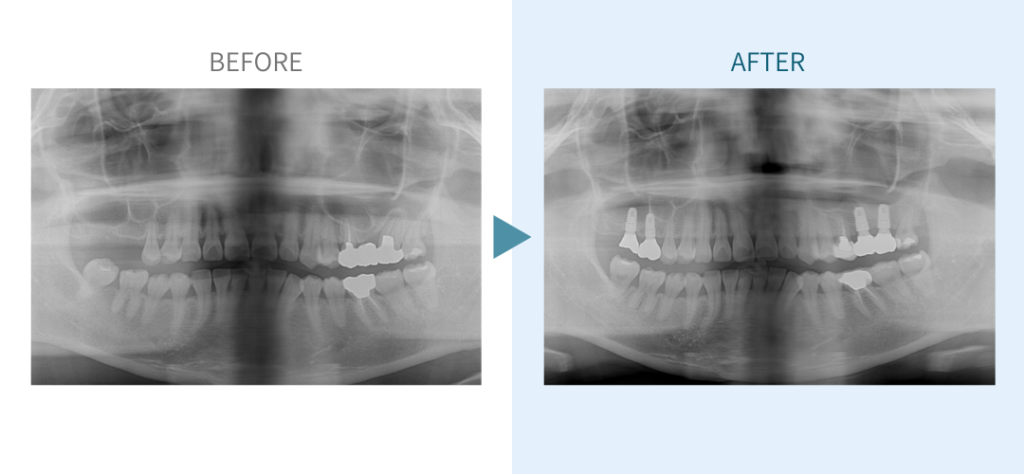

デンタルチームジャパンでは、サイナスリフト(上顎洞底挙上術)や骨造成など、他院で「骨が足りない」と断られた難症例にも対応しています。

私たちは、難症例に関する治療法を学会でも発表しており、その豊富な実績と技術力が評価され、全国から患者様が来院いただいております。

こちらではその一部の症例についてご紹介します。